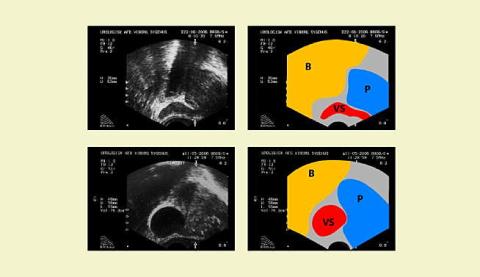

Figuren viser to ultralydskanningsbilleder af prostata foretaget i sagittalplanet og samtidig en skematisk beskrivelse af de samme billeder. Det øverste billede er fra en patient med vandladningssymptomer og normal PSA. Til venstre i billedet ses blæren (B), proksimalt mod højre prostata (P) og i midten en normal vesicula seminalis (VS). Det nederste billede er fra patienten omtalt ovenfor. Til venstre i billedet ses blæren (B), proksimalt mod højre prostata (P) og i midten en tydelig forstørret vesicula seminalis (VS). Billedet må tolkes som afklemning af ductus ejaculatorius i prostata og en deraf følgende dilatation af vesicula seminalis. Den kliniske præsentation af denne cancer blev derfor anejakulation.